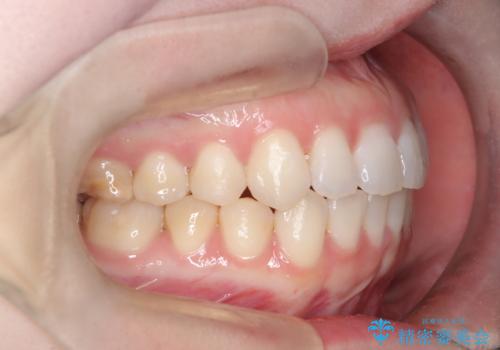

- 右上の八重歯と歯並びのデコボコを気にされて来院されました。精密な検査の結果、歯列のスペースがわずかに不足していることが判明。患者様の「抜歯を避けたい」というご希望を最大限に尊重し、アンカースクリュー(TAD)を用いて奥歯(臼歯部)全体を後方へ移動させることで、八重歯が並ぶスペースを確保する治療計画を立案しました。装置にはワイヤー矯正を使用し、確実で効率的な歯の移動を目指します。

今回のワイヤー矯正治療では、抜歯せずに歯を並べるスペースを作るため、特殊な小さなインプラントであるアンカースクリュー(TAD)を一時的に使用しました。このアンカースクリューを固定源として、奥歯(臼歯部)全体を後方へ遠心移動させました。従来の矯正では難しかったこの奥歯の移動を確実に行うことで、前歯の八重歯を適切な位置に並べるスペースを確保。治療の結果、抜歯することなく右上の八重歯と叢生が解消され、機能的にも審美的にも整った美しい歯並びを獲得していただけました。